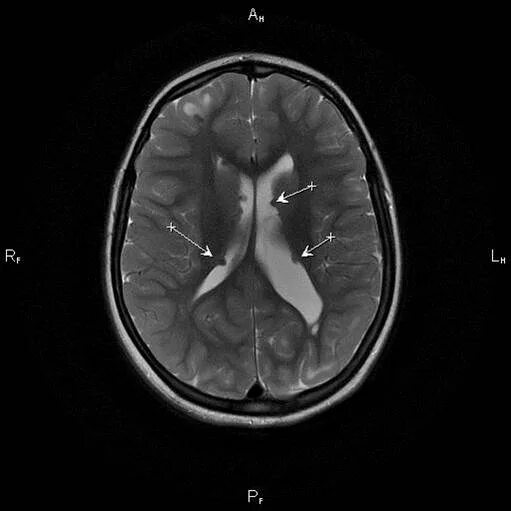

Туберкулезный склероз